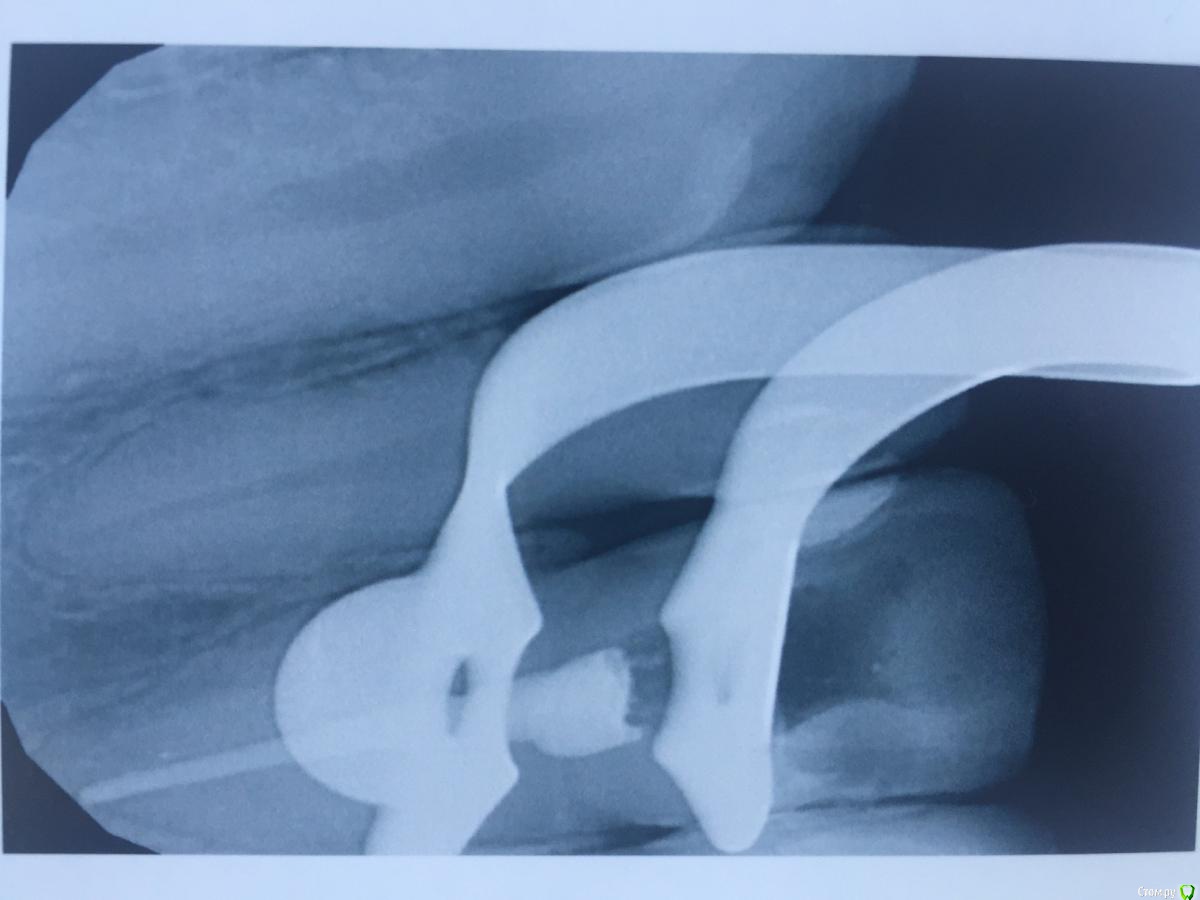

alina39 Опубликовано 9 декабря, 2016 Автор Поделиться Опубликовано 9 декабря, 2016 (изменено) Сделали новую КТ, подтвердился диагноз кистогранулема, почти киста по размерам.В прикрепленных - скриншот кт зуба.А главное боль не проходит, промыли и кальций положили неделю назад а боль не унимается, болит как рана и изредка дергает немного.Был один светлый период - 3 недели назад - когда зуб открыли, сказали полоскать и он неделю после этого не болел совсем, а потом все по новой. Изменено 9 декабря, 2016 пользователем alina39 Ссылка на комментарий

alina39 Опубликовано 9 декабря, 2016 Автор Поделиться Опубликовано 9 декабря, 2016 (изменено) покажите снимки на стадии леченияДругих снимков нет, сначала делали рентген, но на нем кисты не было видно, и потом вот два КТ: первый скриншот - это КТ 3 дня назад, а два других - 3 недели назад. Изменилось ли что-то за эти 3 недели? Изменено 9 декабря, 2016 пользователем alina39 Ссылка на комментарий